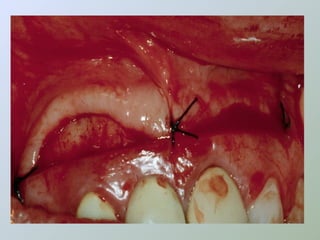

REPOSICIONAMENTO E

SUTURA DO RETALHO

sutura

• Reposicionar o retalho

• Estabilizar com pressão digital

moderada e gaze úmida

• Prevenir a formação de

hematoma sob o retalho e

permitir melhor adaptação e

sutura mais precisa

• Suturas a pontos simples

• Seda 4-0 ou fios

reabsorvíveis

• Após a sutura, comprimir

novamente o retalho com

gaze úmida